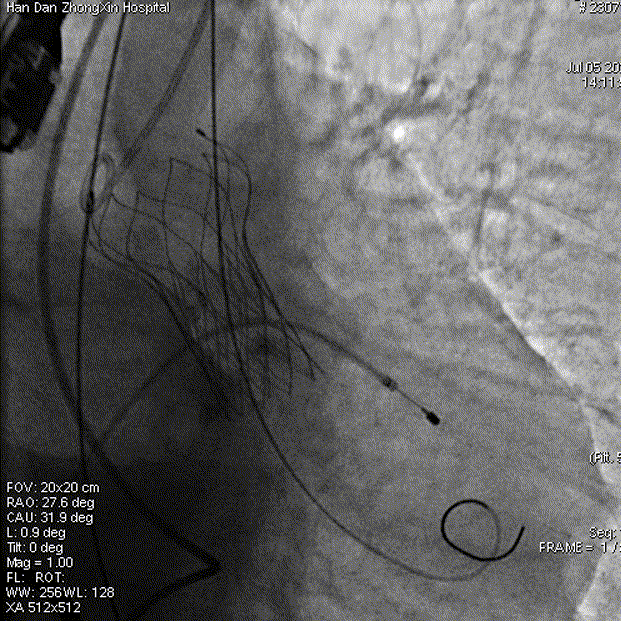

瓣膜释放

释放完成

工作钢丝送入左室进行起搏,180bpm起搏下预扩张主动脉瓣,完全扩张后,主动脉根部造影无返流,回撤球囊停止临时起搏,延大鞘进入输送系统,定位输送系统位置,瓣膜释放1/3时,起搏160bpm,快速释放至3/4处,瓣膜正常工作后,观察冠脉风险。